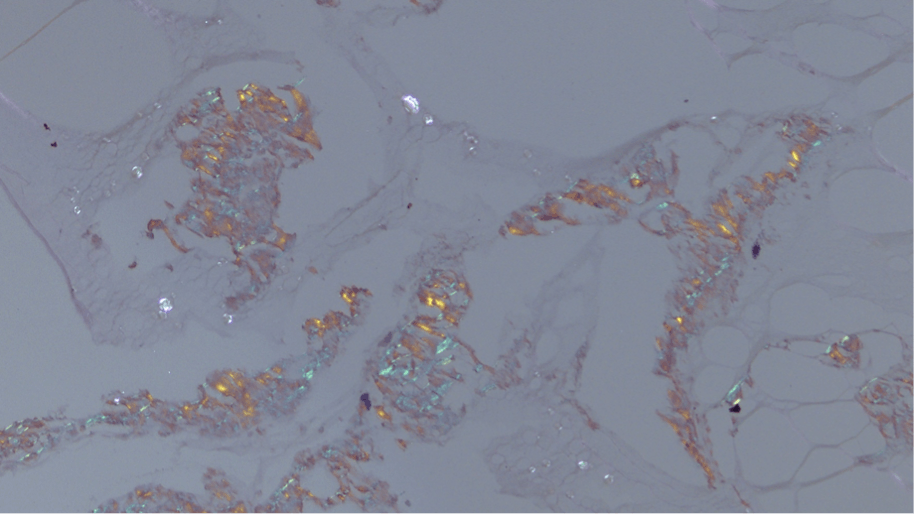

At the 3-month follow-up, the vitreous opacities had worsened. The patient underwent an uncomplicated diagnostic pars plana vitrectomy (PPV). Histopathology results of the vitreous sample did not show neoplastic cells, and no organisms were identified. The sample was also negative for MYD88 mutation. It did, however, demonstrate amorphous eosinophilic material that stained with Congo red, revealing the characteristic red-green birefringence of amyloidosis (Figure 2).

<p>Figure 2. Congo red staining of the vitreous sample shows the characteristic red-green birefringence of amyloidosis.</p>

Figure 2. Congo red staining of the vitreous sample shows the characteristic red-green birefringence of amyloidosis.